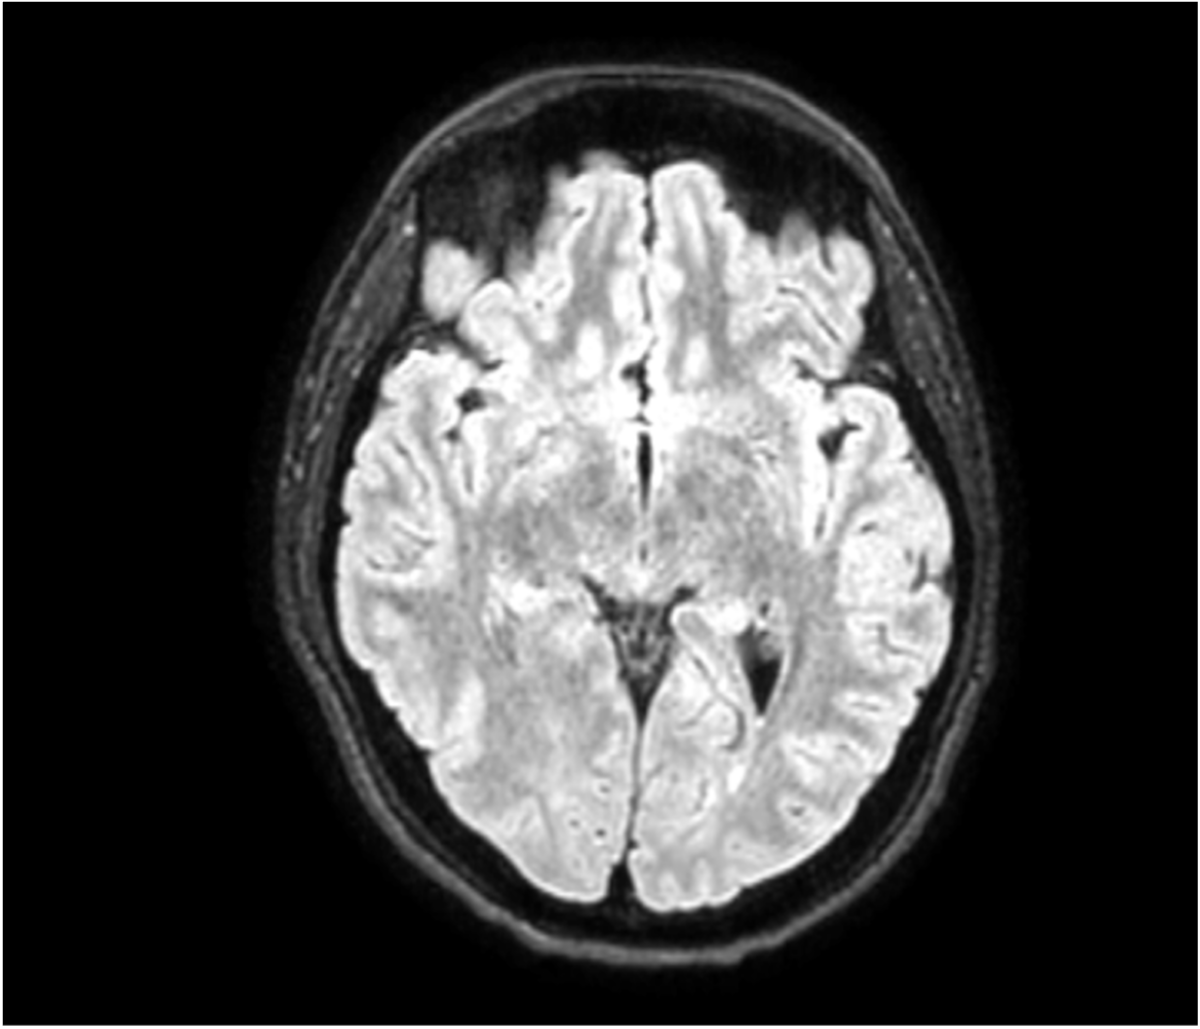

Open-Lip Schizencephaly in Adulthood

Joana Freitas Ribeiro, Cátia Gorgulho, Ana Matos